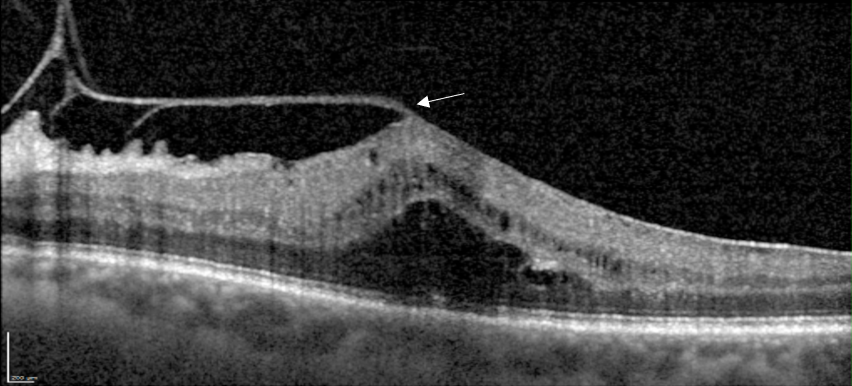

Coupe OCT avec attache vitréo maculaire, épaississement maculaire et disparition de l’entonnoir. Métamorphospies ressenties par le patient.